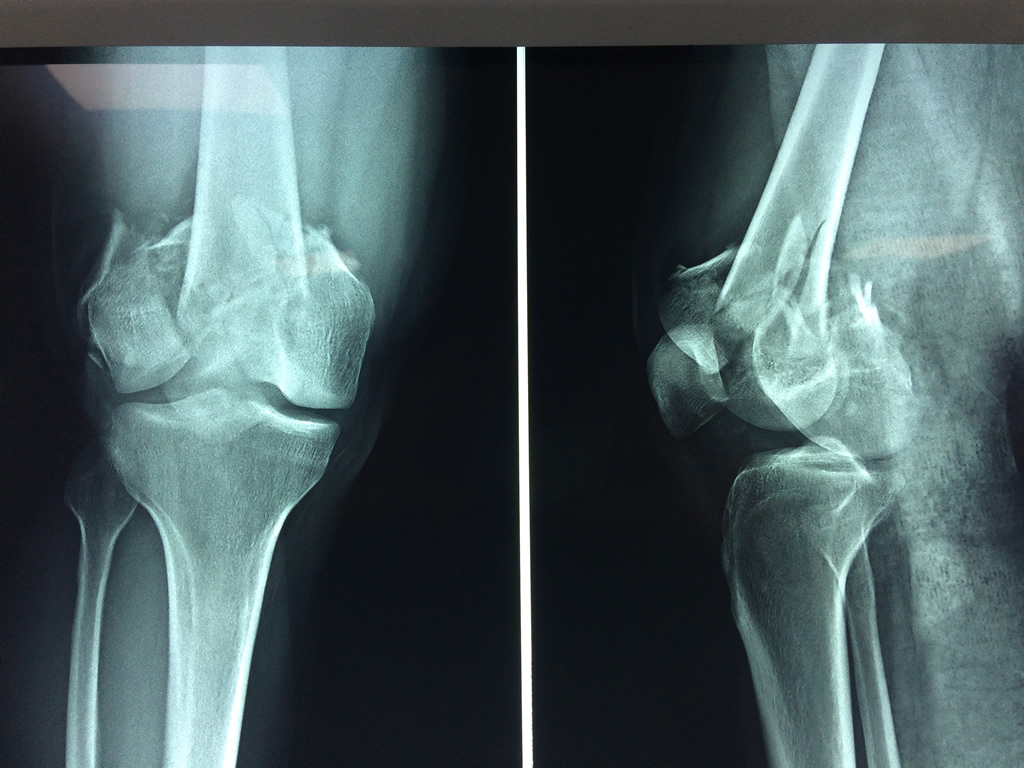

Calcaneo - Fémur

El fémur es el hueso del muslo, el segundo segmento del miembro inferior. Es el hueso más largo, fuerte y voluminoso del cuerpo humano.